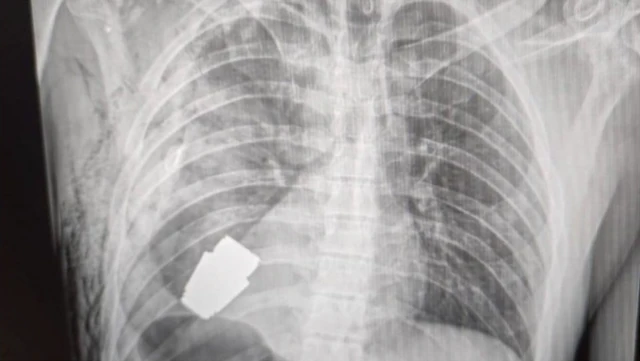

ਯੂਕਰੇਨ ਮਿਲਟਰੀ ਦੇ ਡਾਕਟਰਾਂ ਨੇ ਇੱਕ ਫੌਜੀ ਦੀ ਛਾਤੀ ਵਿੱਚੋਂ ਸਰਜਰੀ ਕਰਕੇ ਇੱਕ ਛੋਟਾ ਗ੍ਰੇਨੇਡ ਸਫਲਤਾਪੂਰਵਕ ਕੱਢਿਆ ਹੈ। ਇਹ ਗ੍ਰੇਨੇਡ ਫਟਿਆ ਨਹੀਂ ਸੀ।

ਇਹ ਇੱਕ ਵੌਗ ਫਰੈਗਮੈਨਟੇਸ਼ਨ ਗ੍ਰੇਨੇਡ ਸੀ ਜੋ ਇੱਕ ਲਾਂਚਰ ਤੋਂ ਫਾਇਰ ਕੀਤਾ ਜਾਂਦਾ ਹੈ।

ਰੂਸੀ ਵੌਗ ਫ੍ਰੈਗਮੈਂਟੇਸ਼ਨ ਗ੍ਰੇਨੇਡ ਸਿਪਾਹੀ ਦੇ ਸਰੀਰ ਵਿੱਚ ਵੱਜਿਆ ਸੀ ਉਸ ਦਾ ਵਿਆਸ 4 ਸੈਂਟੀਮੀਟਰ ਸੀ ਤੇ ਭਾਰ 275 ਗ੍ਰਾਮ ਸੀ।